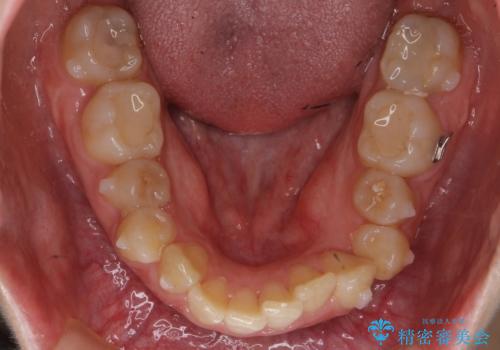

結果それなりに並んで問題ない状況にはなったと思います。

奥歯を後ろに送るために、矯正用ミニスクリューを使用しました。

また、下顎の前歯から奥歯にかけて歯を少し削るIPRを行なっています。

矯正治療開始前におすすめした根管治療の場所がありましたが、患者様の強いご希望により、無視して矯正を開始しました。矯正開始後に、痛みが出て他院で根管治療を行なった影響で、矯正治療を一時中断しました。その影響で矯正治療の期間は長引きましたが、実質一年台で終わったと思います。